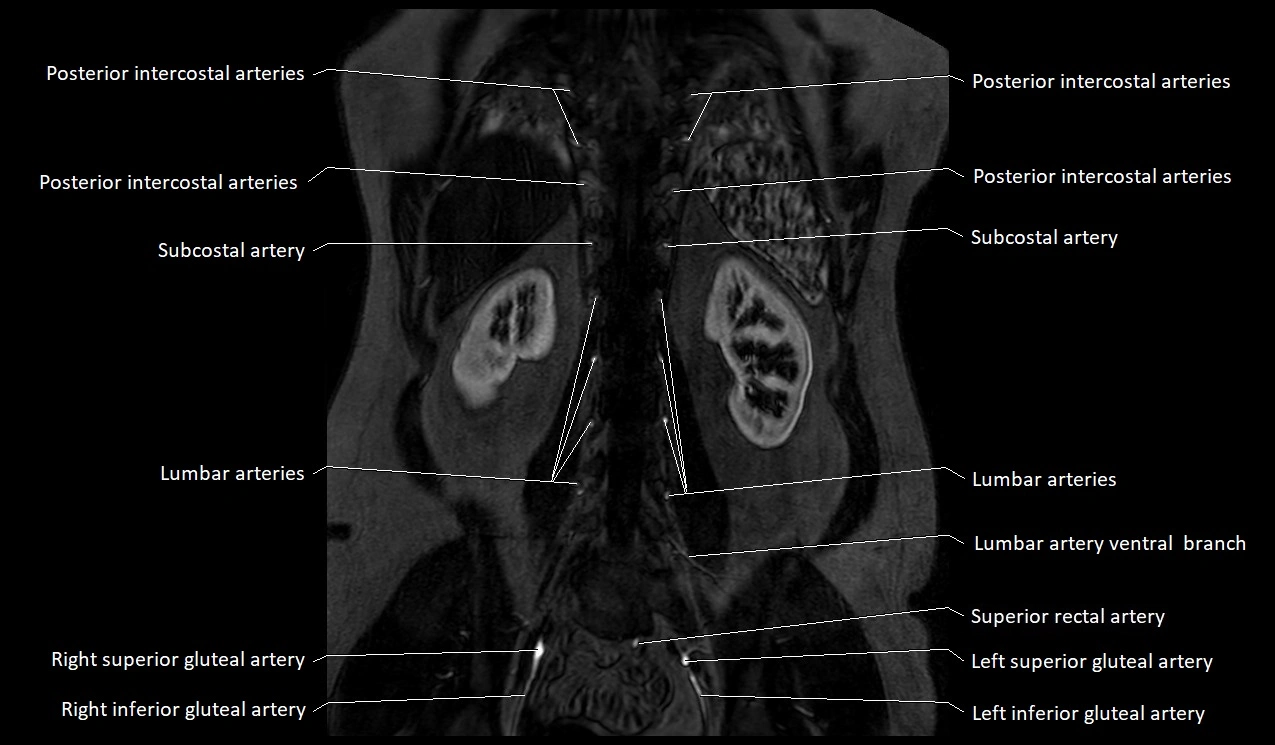

MRI Appearance

T1-weighted images:

Artery appears as a small linear hypointense flow void coursing over the superior pubic ramus

Seen within bright perivascular fat of pelvis

T2-weighted images:

Artery lumen is a signal void

In thrombosed or diseased variants, lumen may appear hyperintense relative to surrounding fat

STIR:

Fat suppression makes the artery more visible within pelvic fat

Helps identify perivascular edema, hematoma, or inflammatory changes

T1 Post-Gadolinium (with fat suppression):

Artery enhances brightly and homogeneously

Useful for tracing the course, anastomoses, and presence of corona mortis

Highlights arterial wall thickening or tumor encasement if present

MRA Pelvis with Gadolinium:

Clearly delineates the origin, course, and anastomoses of the accessory obturator artery

Identifies connection with inferior epigastric artery, external iliac artery, or obturator artery

Excellent for detecting vascular variants prior to surgery

Useful in mapping pelvic vasculature in trauma, tumor embolization, or preoperative planning